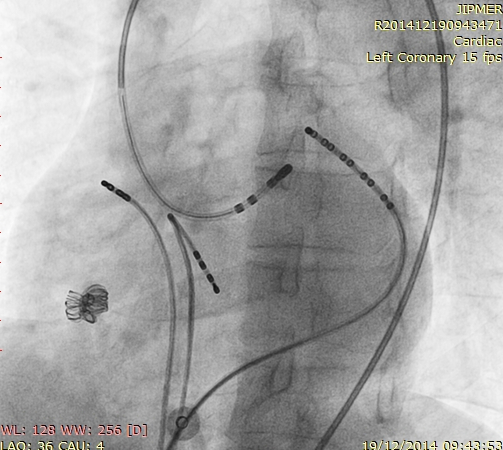

Start with a deeply placed CS catheter

cs_catheter.jpg

Deflectable sheath in CS